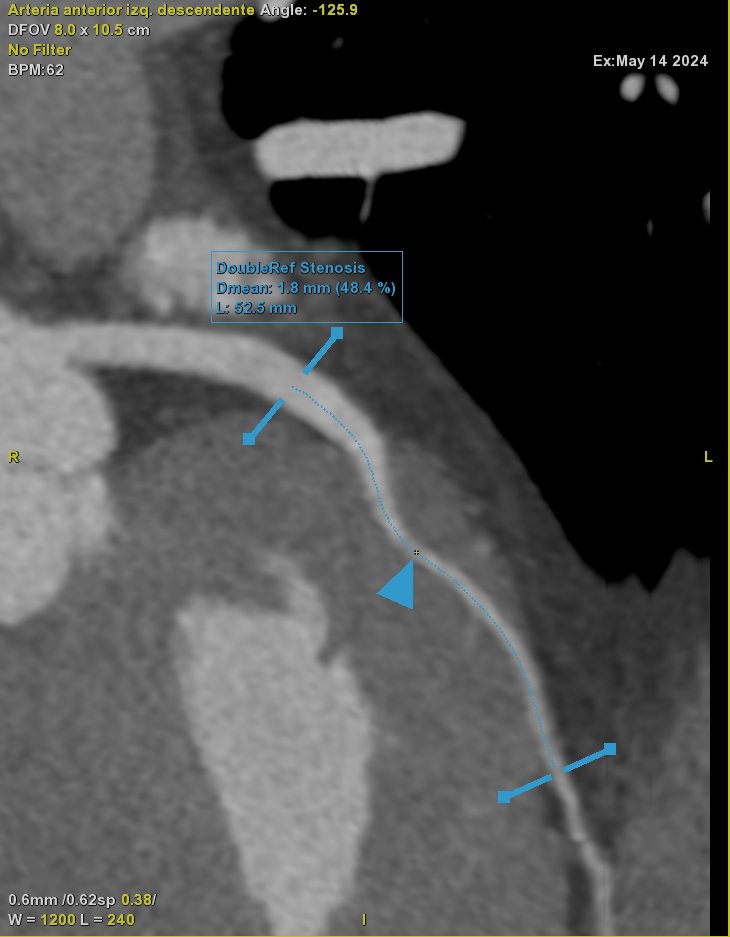

First day in #ICNCCT2024 meeting and honored to participate in the astonishing clinical case sessions after 2 years of the beggining of our CCTA program 👏👏👏Hospital Universitario Poniente